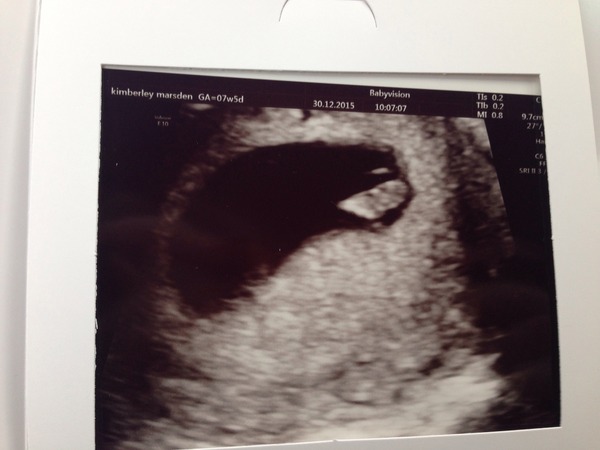

Well I'm measuring at 7+2 so only 3 days different to my estimations from LMP. Got to see and hear a heartbeat, balled my eyes out once I got outside. I feel so weird now, I knew I was pregnant but now I KNOW I'm pregnant!!! And it's only one huzzah!!!

TCC#1 Grads Thread